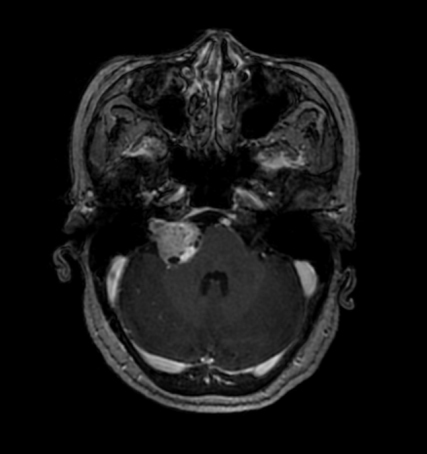

术前

62岁的女性患者李某系毕节市纳雍县人,近6年来,右侧听力逐渐下降,以为是随着年龄的增长导致的正常现象,并没有重视,后来出现右侧面颊部疼痛,呈间断性针刺样,伴右脸麻木感。在外院行颅脑MRI示:右侧桥小脑角区占位,内听道扩大。

进一步完善相关检查,患者被明确确诊为颅内占位性病变:右侧听神经瘤。